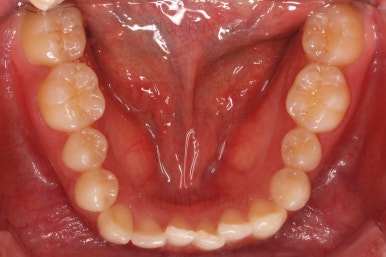

초진 시 입안의 모습이에요.

위아랫니가 모두 삐뚤어요.

특히 앞니가 삐뚤고 위아래 앞니가 고르게 덮여있는게 아니라 뒤죽박죽 엉켜있어서 치아의 마모도 굉장히 많이 되어있는 상태였어요.